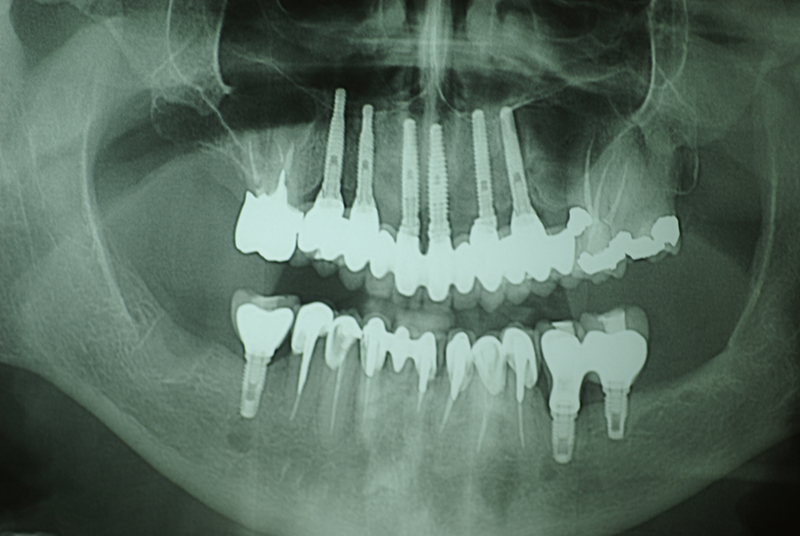

Na Clínica Pontes Odontologia, somos referência em implantes dentários em Fortaleza, oferecendo tratamentos de alta qualidade e tecnologia de ponta. Os implantes dentários são estruturas de titânio posicionadas cirurgicamente no osso maxilar ou mandibular para substituir as raízes dos dentes ausentes. Essa técnica permite a fixação de próteses personalizadas, restaurando a função mastigatória, a estética e a autoestima dos nossos pacientes.

Utilizamos a tecnologia CAD CAM, um sistema avançado que possibilita a confecção precisa das próteses dentárias diretamente sobre os implantes. Esse método inovador garante um ajuste perfeito, um resultado estético superior e proporciona muito mais conforto e durabilidade. Com o CAD CAM, nossos pacientes contam com um processo mais rápido e previsível para alcançar o sorriso desejado.